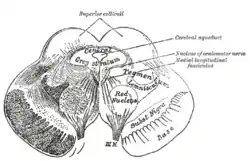

Transverse section of mid-brain at level of superior colliculi. ("Tegmentum" visible center right.) | |